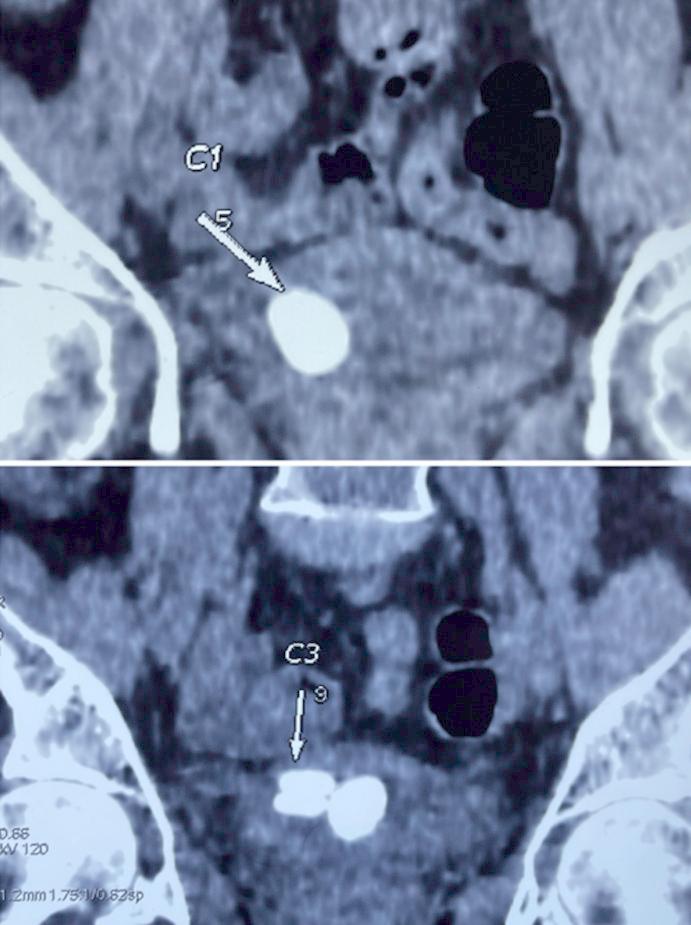

In recent years, the utilization of enterocystoplasty for bladder function enhancement has increased, albeit accompanied by risks such as stone formation, necessitating vigilant follow-up. We report a case of a 60-year-old female with a neobladder who presented with back pain, constipation, and pelvic heaviness, revealing multiple large stones in imaging. Stone analysis showed calcium oxalate and magnesium. Enterocystolithotomy was performed to manage the condition. Enterocystoplasty, a standard treatment for bladder cancer, can lead to stone formation due to factors like urinary stasis and infections. Giant stones are rare but require prompt treatment, often involving neocystolithotomy. Controlling risk factors and selecting appropriate treatment based on stone size and surgical expertise are key to improving patient outcomes.

近年来,利用肠膀胱扩大术来增强膀胱功能的应用有所增加,但也伴随着结石形成等风险,需要密切随访。我们报告了一例 60 岁女性的病例,她患有新膀胱,出现背痛、便秘和骨盆沉重感,影像学显示有多个大结石。结石分析显示为草酸钙和镁。行肠膀胱切开取石术治疗该疾病。肠膀胱扩大术是膀胱癌的标准治疗方法,但由于尿液淤滞和感染等因素,可导致结石形成。巨大结石较为罕见,但需要及时治疗,通常需要行新膀胱切开取石术。控制风险因素并根据结石大小和手术专业知识选择适当的治疗方法是改善患者预后的关键。